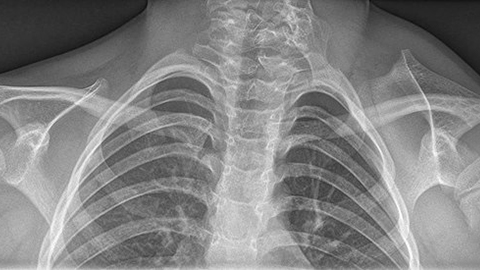

0:05:19.7 RW: And the consequence is that the scapula on that side doesn't form normally. And it might be hypoplastic, that is, smaller than a normal scapula. Remember hypo means below, and plastic means shape. It turns out that if this happens to the scapula, then hypoplasticity will probably also affect all the muscles that attach to that scapula. And there are a few other things that we see with Sprengel's deformity as well. This condition often appears with some other musculoskeletal abnormalities, including Kliplofile syndrome, scoliosis and spina bifida. Kliplofile syndrome is a new one on me. This is an anomaly in which two or more cervical vertebrae are fused, and this leads to a really shortened neck and a limited range of motion and pain. I have included an artist's rendering of an MRI taken from a person who had both Sprengel's deformity and Kliplofile syndrome, so you can see how these situations affect the shoulder girdle. And of course you will find that in our show notes. Sprengel's syndrome is rare.